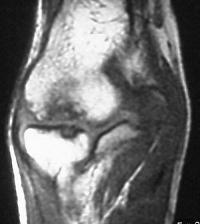

MRI shows an osteochondral sequestrum of the anterior capitellum:

Treatment options? Do nothing, Open reduction and bone graft, sequestrum excision or radial head excision. In this case, at surgery, the loose articular fragment was too thin to allow reliable fixation, and was simply excised.